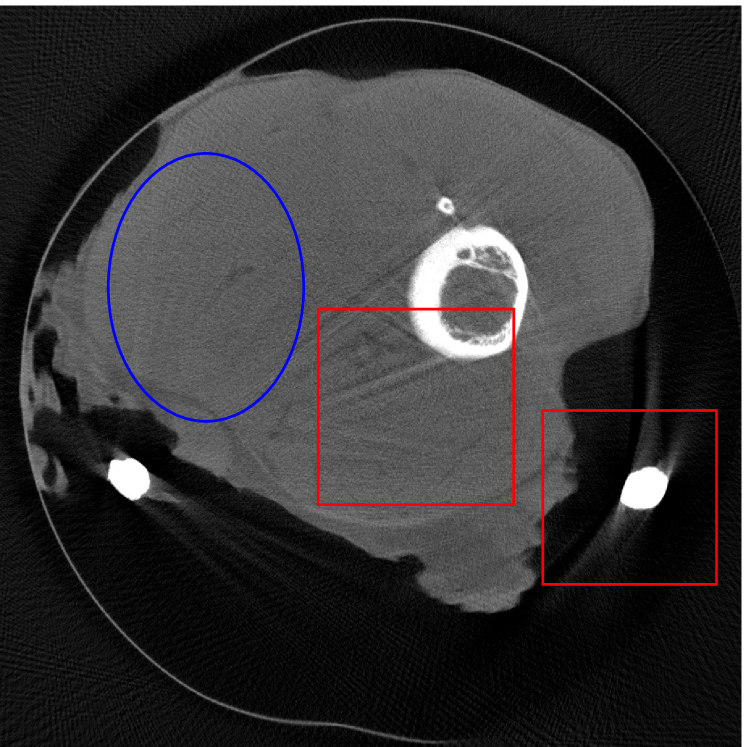

4.2 Numerical experiments: real data

We perform a CT scan of a chicken leg placed in a disposable cup (Figure 10(a)). We first scan the chicken leg without metals (Figure 10(b)) to create a reference image using FBP algorithm. Then, we place two steel thread nails on each side of the chicken leg and scan the subject again using the same scanning protocol (Figure 10(c)). The projection data is acquired from a MicroCT scanner equipped at the Division of Nuclear Technology and Applications, Institute of High Energy Physics, Chinese Academy of Sciences. The X-ray source is with 90 kV and 70 mA energy and the flat plane detector contains pixels. The scanning trajectory is a full circle with equally spaced views at per view. The physical size of each detector unit is . The distance from the X-ray source to the detector is . In order to conduct a 2D experiment, we choose the 512th row of the detector array.

Figure 11 shows the images reconstructed using FBP, the analysis model (2.12), the inpainting model (2.13) and the segmented image from the image obtained by (2.14). The reference image without metal implants are shown in Figure 11(a). All the images in this subsection are displayed within the grayscale interval . The segmented image shown in Figure 11(e) is used to estimate the weights needed in NMAR and the re-weighted JSR model.

Figure 12 shows a comparison between the reconstructed image from NMAR and the unweighted JSR model. Figure 13 shows a comparison between the reconstructed images from TV-FADM and the proposed re-weighted JSR model. Zoom-in views are provided in both Figure 12 and Figure 13 for a better visual assessment. As one can see that the reconstructed images from the unweighted JSR model and TV-FADM are less noisy than NMAR as indicated by the blue ellipse curve, whereas NMAR does a better job in preserving image features and suppressing metal artifacts. However, there are also new artifacts around the metal on the right as shown in Figure 12(d). The proposed re-weighted JSR model has best overall performance in terms of feature preservation, noise and metal artifact reduction.